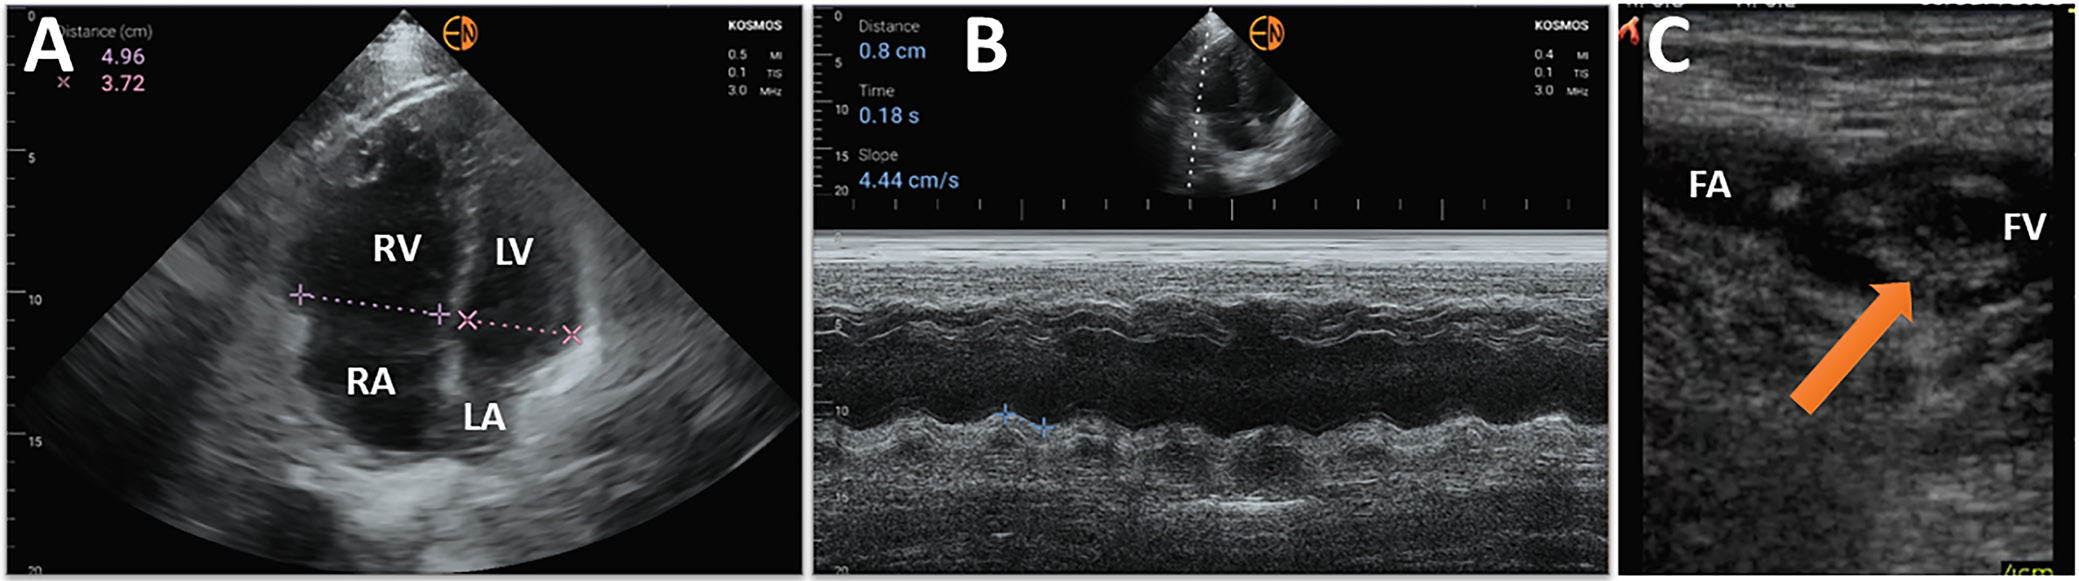

In the majority of cases, the assessment of LV systolic function is qualitative, based on visual estimation of LVEF and regional wall motion. This task proved to be one of main interests of authors attempting to make HUD-acquired echocardiography analysis a fully automated process. Certain HUDs (e.g., VScan Extend; GE Healthcare, Lincoln Park, USA) offer a downloadable application which enables an automated edge detection of left myocardial wall and calculates the end-systolic and end-diastolic left ventricular volumes and LVEF using apical 4-chamber views. Good agreement between HUD and 3D measurement of LVEF on stationary echocardiography was identified12, 13; however, the results largely depended on the quality of acquired images. Furthermore, in almost 12% of patients, the software failed to calculate LVEF.12 A more advanced algorithm available on other device (Kosmos; Echonous, Redmond, USA) performed an automated EF calculation from 2 apical projections, which showed good agreement with measurements using Simpson’s method. Other clinical benefits of this software include high-specificity and high-sensitivity detection of patients with decreased LVEF.14 Improvements to the algorithm also enable a semi-automated EF by editing the endocardial borders, which might prove clinically relevant but requires further validation (Figure 1).